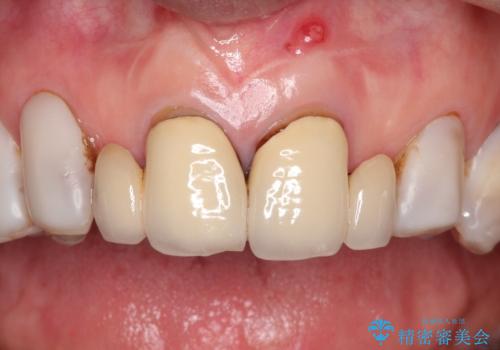

【オールセラミッククラウン】前歯を綺麗にしたい。

- 前歯の被せもののやりかえを主訴に来院されました。

前歯の歯茎から膿も出ていたため、歯内治療を行なったのち修復を行なっております。

根管治療および外科的歯内療法を行なってから被せものの処置を行なっております。